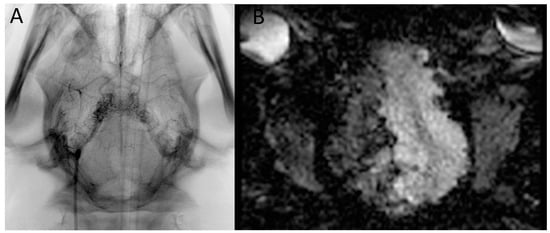

DSA run confirmed the filling of the RM and right-sided intracranial ICA, MCA, and ACA with slight reflux to the left side and posterior circulation (Figure 1).

Figure 1.

Test infusions through Apollo microcatheter under (A) X-ray and (B) real-time dynamic EPI-GRE MRI monitoring—dynamic images available in the Supplementary Material Video S1.

T2 anatomical sequences and X-ray picture confirmed Onyx cast distribution at the end of the procedure (Figure 3).

Figure 3.

FU T2 scans 20 min after Onyx injection and an X-ray image of the Onyx cast.